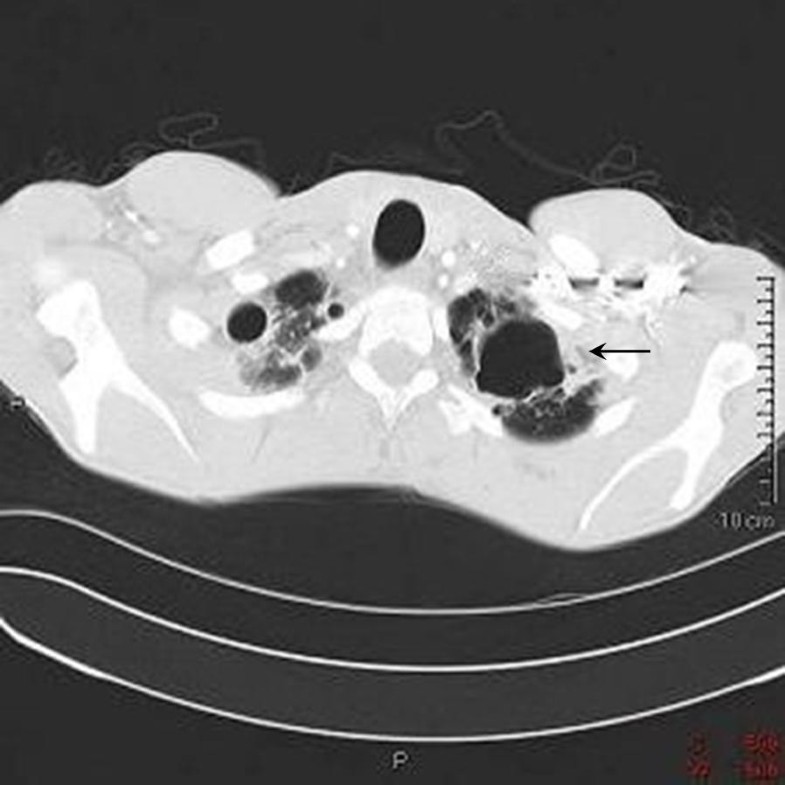

Web evidence that chronic cannabis users have an increased incidence of respiratory symptoms such as chronic. Aeruginosa cap include smoking, alcohol use, obstructive lung disease, sinusitis, and hot tub use. Web the data reveal that risk factors for p. Web we report a case of marijuana smoking via a bong device, which has resulted in severe pseudomonas aeruginosa.

Lung Soreness Due To Bong Use - Web the data reveal that risk factors for p. Web we report a case of marijuana smoking via a bong device, which has resulted in severe pseudomonas aeruginosa. Web evidence that chronic cannabis users have an increased incidence of respiratory symptoms such as chronic. Aeruginosa cap include smoking, alcohol use, obstructive lung disease, sinusitis, and hot tub use. Web this.